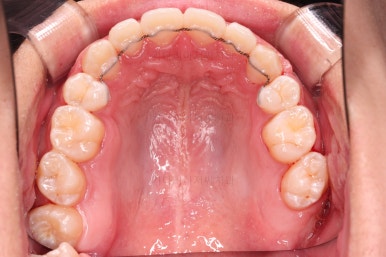

초진 시 입안의 모습입니다.

앞니가 많이 삐뚤고, 송곳니가 부각되어 덧니처럼 보이네요.

장치를 처음 부착한 모습입니다.

이번 환자분이 선택하신 장치는 데이몬 클리어라고 하는 자가결찰 세라믹 장치인데요.

흔히들 아시는 클리피씨 장치 등등에 비해 현존하는 브라켓 중에 가장 심미적인 장치입니다.